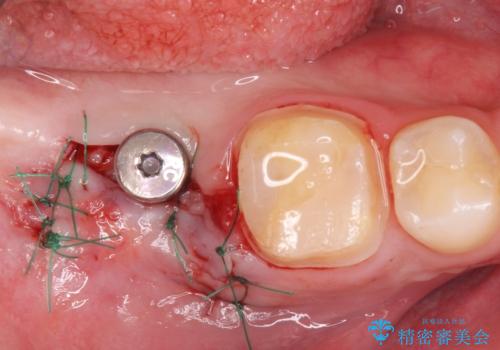

手前の銀の詰め物のところは除去して拡大鏡下で虫歯を取り除き、ジルコニアクラウンで治療を行いました。

抜歯したところは抜歯後骨の治癒を待ち、CTを撮影しインプラント治療ができる事(骨の厚みなど)確認し治療を行いました。

インプラントを入れた後は定期的なメンテナンスが必要になります。

- 外科手術のため、術後に出血、痛みや腫れ、違和感を伴います